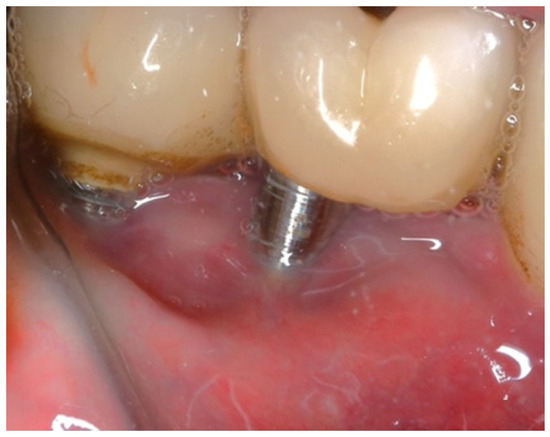

In this case, after achieving the renewed implant surface (machined), the regenerative procedure involving bone grafting and collagen membrane was not performed. The flaps were repositioned and secured with tension-free primary closure. The postoperative instructions included chlorhexidine 0.12% (Taro Pharmaceuticals, Haifa Bay, Israel) rinses and systemic antibiotic coverage for 5 days. Regular clinical and radiographic evaluations were conducted at 1 month, 3 months, 6 months, and 12 months, postoperatively. At the six-month follow-up, the clinical examination revealed significant improvements, with resolution of inflammation and no BoP; the patient reported a complete resolution of the initial chief complaints. Radiographs demonstrated stabilization and initial signs of bone regeneration around treated implants. At the 12-month follow-up, the bone level and PDs were stabilized (Figure 23), and the implant surface adequately accommodated the gingival tissue (Figure 24).

Figure 24. (a) Clinical follow-up after 12 months; (b) Radiographic outcome after 12 months.